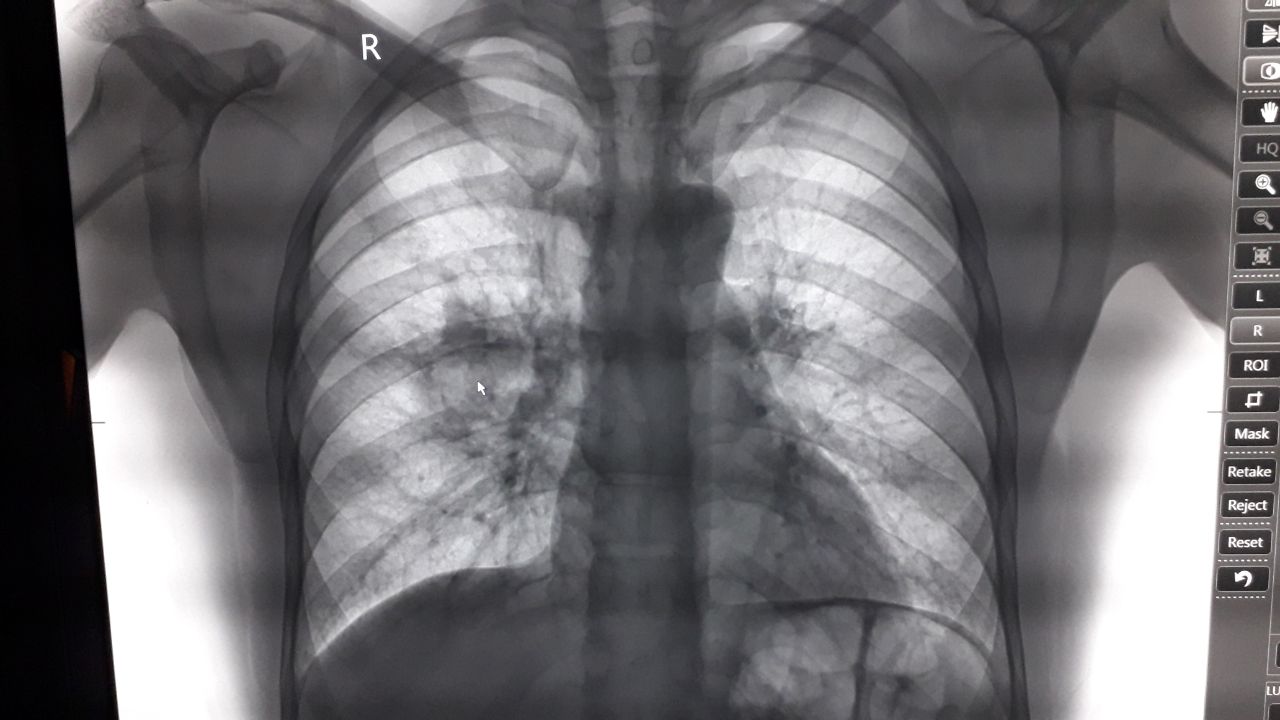

Мтs лёгких